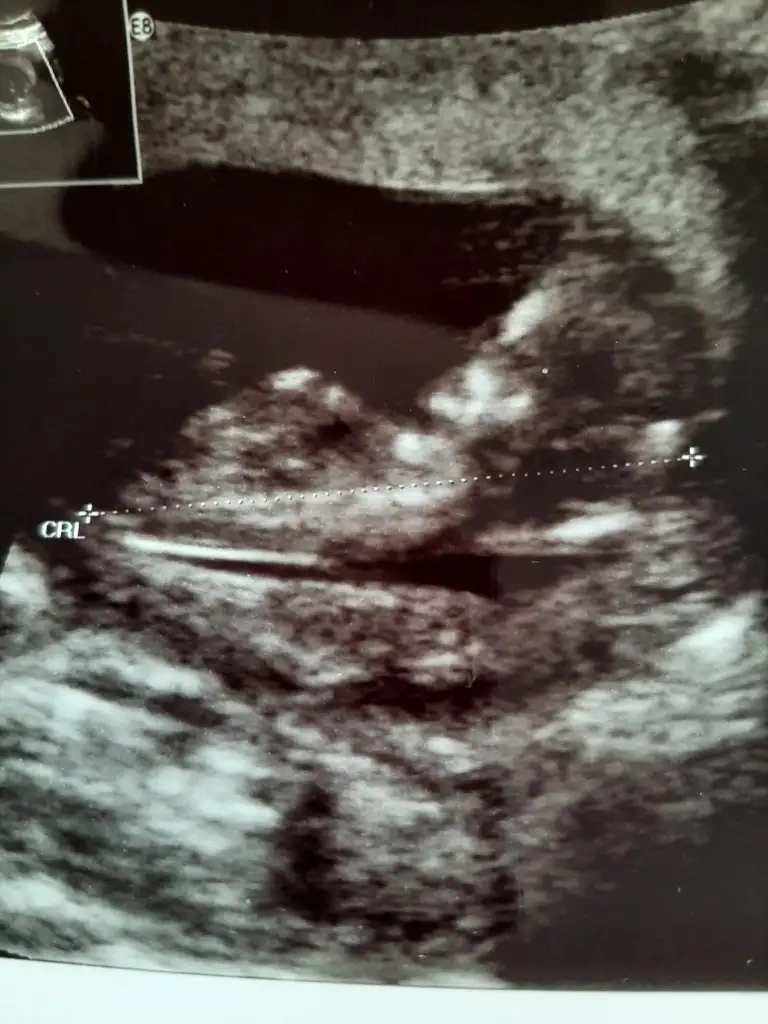

T tulperde Bana da bakarsan cok sevinirim arkadaşim🤗🥰🙈 12 hafta ultrason karindan:) doktor yorum dahi yapmadi goremedi sanirim🙂

Eklentiler

• 16255793651197909157825059345704.webp

16255793651197909157825059345704.webp

35,4 KB · Görüntüleme: 50